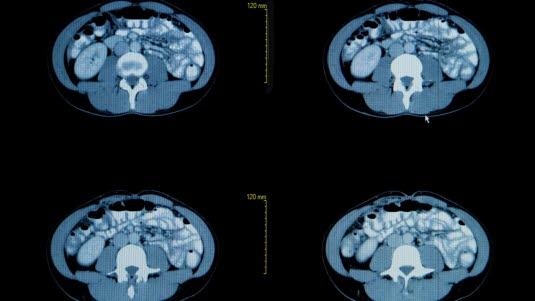

CT bilder er svarthvite. Organene fremstilles i ulike grader av grått. Vev med lav tetthet, f.eks. luftfylte hulrom, vises som mørke eller svarte partier. Vev med høyere tetthet vises i lysere gråtoner. Jo høyere tetthet, jo lysere. Beinvev fremstilles hvitt.

Siden CT kan skille mellom ulike indre organ, såkalte bløtdeler, så kan CT av brysthulen (thorax) gi detaljerte tverrsnittsbilder og tredimensjonale bilder av lungene, bronkiene (luftrørene), lungehinnen (pleura), strukturer i midtre del av brysthulen (mediastinum) og hjertet. Bildene fremstår i ulike nyanser av grått. Jo lysere skygge, jo høyere tetthet har vevet eller strukturen. Bildekvaliteten kan forbedres ved samtidig bruk av kontrastinjeksjon.